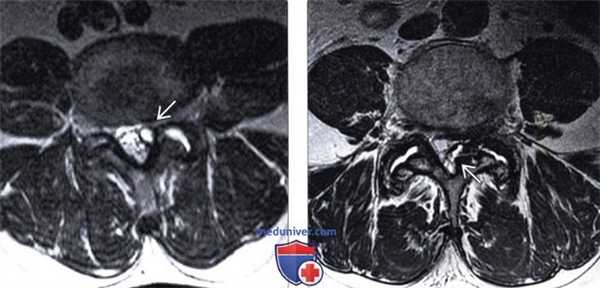

(Справа) Аксиальный срез, Т2-ВИ: с насыщением жировой ткани видны признаки выпота в полости левого дугоотростчатого сустава В с распространением и локуляцией жидкости кзади от сустава. Видны признаки отека окружающих мягких тканей. (Слева) Сагиттальный срез, STIR МР-И: признаки многоуровневого спондилодисцита с жидкостными скоплениями в межтеловых промежутках и эрозивными изменениями смежных замыкательных пластинок. Также имеются признаки инфекционного поражения дугоотростчатых суставов двух смежных уровней. В полости суставов определяется свободная жидкость. Определяются признаки отека костного мозга суставных колонн, а также окружающих мягких тканей.

(Справа) Сагиттальный срез, Т1-ВИ: FS с КУ: признаки периартикулярных воспалительных изменений, связанные с септическим артритом дугоотростчатого сустава. Эпидуральная флегмона распространяется в межпозвонковое отверстие.